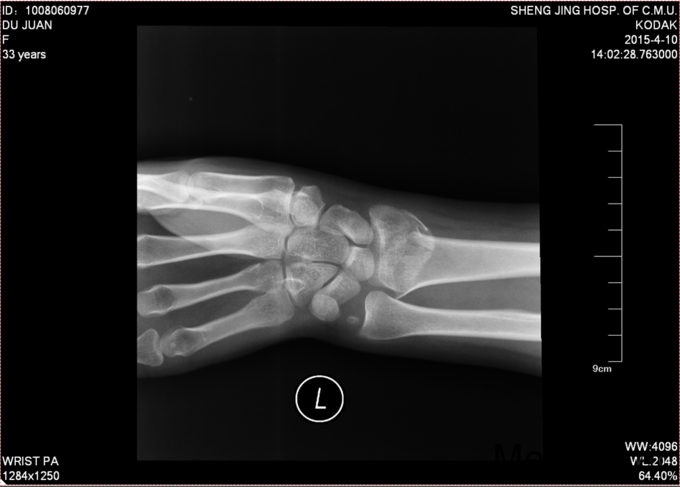

主诉:摔伤后左腕部疼痛活动受限4小时。现病史:4小时前行走时不慎摔倒,手掌着地,导致左腕部疼痛肿胀活动受限,家人急送至我院急诊,行左腕部DR时:桡骨远端骨折。现患者为求进一步诊治要求住院治疗,我科以“科雷斯(colles)骨折”为主要诊断收入我科。患者自受伤以来,无发热,无呼吸困难,饮食睡眠正常,大便未排,小便正常。

患者右手托左腕部步入病房,左腕部肿胀,疼痛(+),压痛(+),骨擦音(+),骨擦感(+),活动受限,皮肤感觉无异常,手指活动灵活,双侧桡动脉可触及。

诊断:科雷斯骨折;治疗:手法复位,石膏固定

术后给予患者止疼消肿等对症治疗,石膏固定后2周后给予复查腕关节正侧位DR,位置良好,更换功能位短石膏。